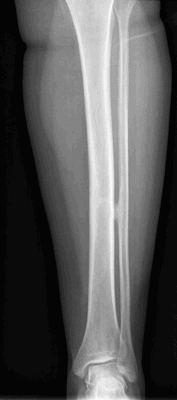

Крупная остеохондрома проксимальной части малоберцовой кости: рентгенограмма (а), трехмерная КТ-реконструкция (б), КТ-срез (в). Образования этой локализации могут стать причиной нейропатии малоберцового нерва.

В данном случае имеется выраженная вогнутая деформация прилежащего кортикального слоя большеберцовой кости, являющаяся примером вторичной деформации кости вследствие экспансивного роста остеохондромы. Остеохондрома на ножке дистального отдела бедра. Образования обычно растут в противоположную от суставов сторону. Спонгиозная часть остеохондромы сообщается с костно-мозговым каналом пораженной кости. Образование сохраняет единство кортикального и спонгиозного слоя с материнской костью, что является рентгенологическим признаком остеохондромы. Остеохондрома на широком основании дистального конца большеберцовой кости. Обратите внимание на угловую деформацию пилона большеберцовой кости. Образования подобной локализации могут приводить к нарушению роста и угловой деформации костей. Множественный остеохондроматоз, сопровождающийся деформацией костей. Это наследственное заболевание с аутосомно-доминантным типом наследования. Пациент с симптоматикой, обусловленной компрессией большеберцового нерва. Рентгенограмма коленного сустава пациента с множественными остеохондромами. Имеются множественные поражения дистального отдела бедра и проксимального отдела большеберцовой кости и сопутствующая деформация конечности. Интраоперационная картина остеохондромы. Обратите внимание на непрерывность кортикального слоя и «шапку», образованную зрелой хрящевой тканью. Микропрепарат остеохондромы. Гистологически эти образования выглядят также, как зоны роста костей — хрящевая ткань, созревающая путем энхондрального окостенения и превращающаяся в нормальную костную ткань. Макропрепарат остеохондромы. Обратите внимание на хрящевую «шапку» с сохранением непрерывности костно-мозгового пространства остеохондромы и пораженной кости.